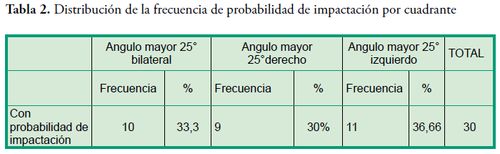

Los pacientes que presentaron probabilidad de fracaso en la erupción corresponden al 1,43% de la muestra, su edad promedio fue de 10 ± 1,7 años, en relación al sexo el 73,3% son mujeres. La variable que se utilizó para determinar la probabilidad de éxito o fracaso en la erupción fue el ángulo del segundo molar: -menor o igual a 24° se consideró probabilidad de erupción exitosa, mientras que -un ángulo de 25° o más se consideró con probabilidad de fracaso en la erupción de acuerdo al promedio manifestado por Evans en 1988 (promedio de 25° con un rango entre 15° a 65°). Las Tablas 1, 2 y 3 expresan los resultados de las variables indagadas y su relación con la probabilidad o no de erupción, la presentación en forma uni o bilateral y su distribución por cuadrante.

Los pacientes que presentaron probabilidad de fracaso en la erupción corresponden al 1,43% de la muestra, su edad promedio fue de 10 ± 1,7 años, en relación al sexo el 73,3% son mujeres. La variable que se utilizó para determinar la probabilidad de éxito o fracaso en la erupción fue el ángulo del segundo molar: -menor o igual a 24° se consideró probabilidad de erupción exitosa, mientras que -un ángulo de 25° o más se consideró con probabilidad de fracaso en la erupción de acuerdo al promedio manifestado por Evans en 1988 (promedio de 25° con un rango entre 15° a 65°). Las Tablas 1, 2 y 3 expresan los resultados de las variables indagadas y su relación con la probabilidad o no de erupción, la presentación en forma uni o bilateral y su distribución por cuadrante.

Existe una baja prevalencia de segundo molar inferior con probabilidad de impactación. La invasión a la cara distal del primer molar en el presente estudio fue mayor a lo encontrado en otras investigaciones. La probabilidad de impactación se presenta con mayor frecuencia en forma unilateral. Se observó mayor frecuencia de probabilidad de impactación del lado izquierdo. No se encontró relación entre tamaño del espacio distal del primer molar con el borde anterior de la rama mandibular y la probabilidad de impactación del segundo molar.

Existe una baja prevalencia de segundo molar inferior con probabilidad de impactación. La invasión a la cara distal del primer molar en el presente estudio fue mayor a lo encontrado en otras investigaciones. La probabilidad de impactación se presenta con mayor frecuencia en forma unilateral. Se observó mayor frecuencia de probabilidad de impactación del lado izquierdo. No se encontró relación entre tamaño del espacio distal del primer molar con el borde anterior de la rama mandibular y la probabilidad de impactación del segundo molar.